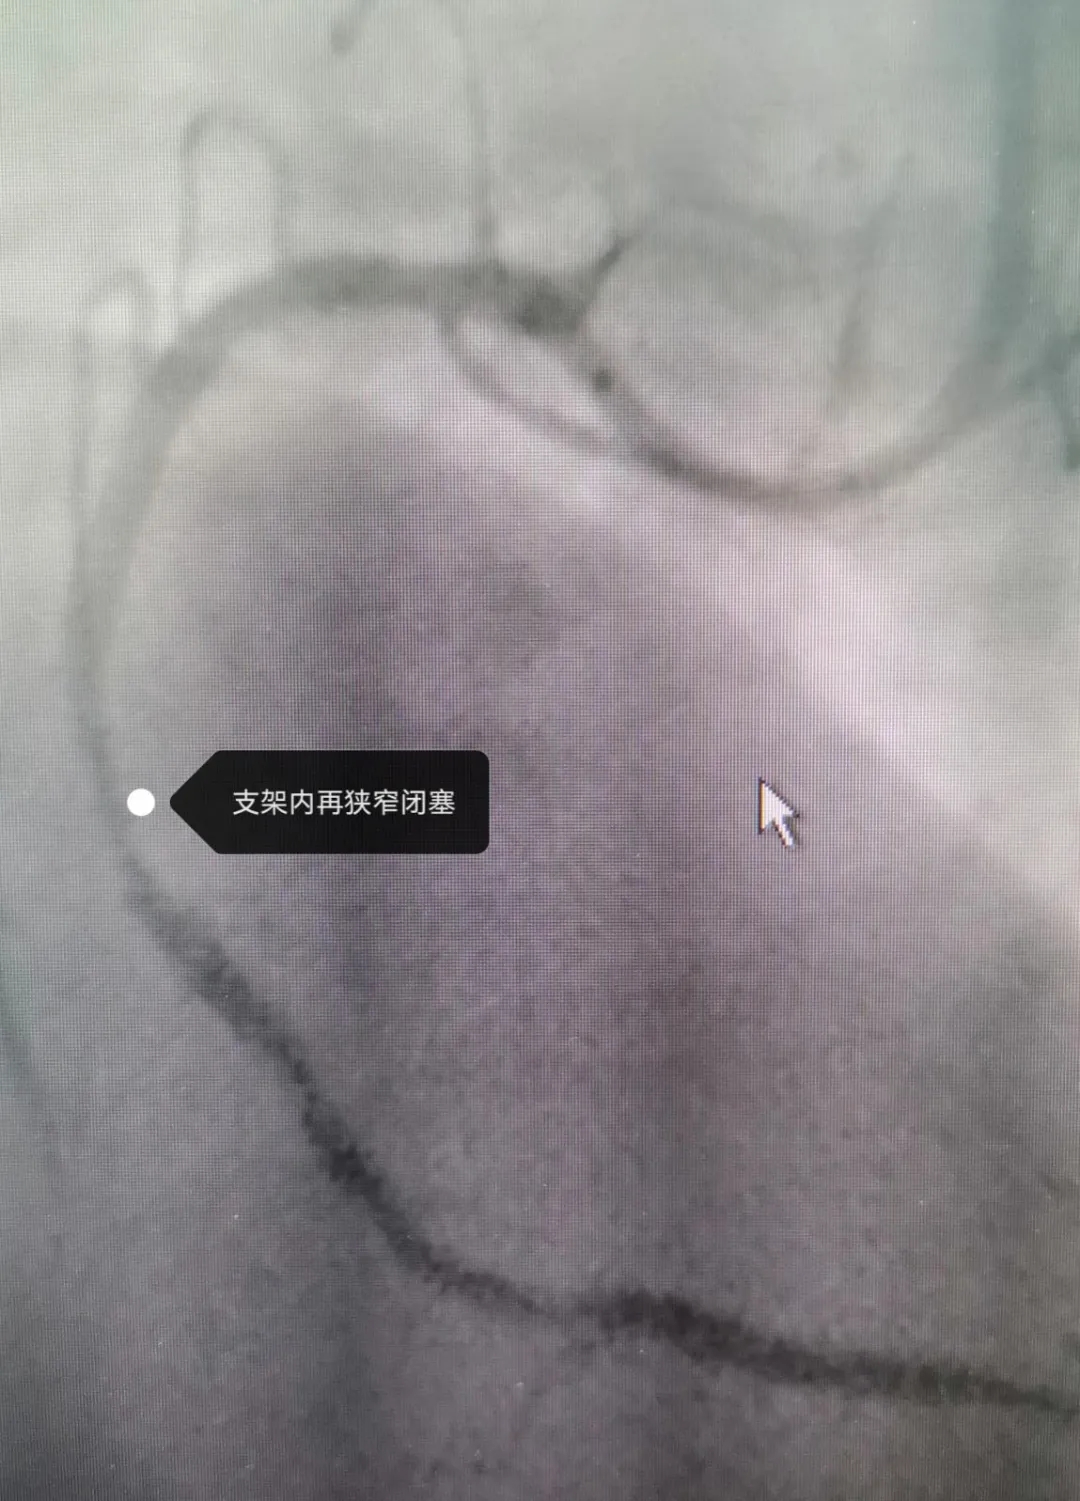

早在2022年9月30日

他就因“急性下壁心肌梗死”

接受過冠狀動脈內(nèi)支架植入術治療